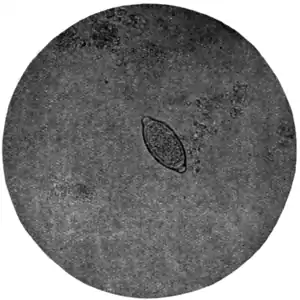

Fig. 170.—Ovum of Trichiuris trichiura, x 280. (Photograph by Dr. J. Bell.)

Ova of Trichiuris trichiura (Fig. 168, c).—Of the three common nematodes mentioned—Trichiuris trichiura, Ascaris lumbricoides, and Ankylostomum duodenale—the ova of the first are the most frequently met with. They occur sometimes in enormous numbers, as many as six or eight specimens being visible in one field of an inch objective. They form a rather striking object under the microscope (Fig. 170). They are oval, measuring 51 to 54 μ by 21 to 23 μ, the ends of the long axis of the oval being slightly pointed and tipped with a little shining projection or plug. Their general appearance suggests an elongated oval tray, the projections at the poles of the ovum representing the handles of the tray. They are dark brown in colour, sharply defined, doubly outlined, and contain no differentiated embryo.